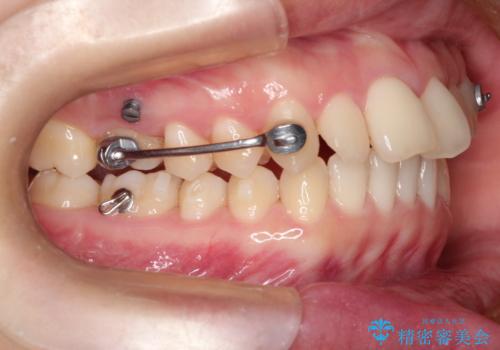

奥歯の嚙み合わせのズレを改善するにあたり、カリエールディスタライザーという装置を併用することで治療期間の短縮を図りました。

カリエールディスタライザーは臼歯の位置関係において理想とのズレが多い場合に有効となります。